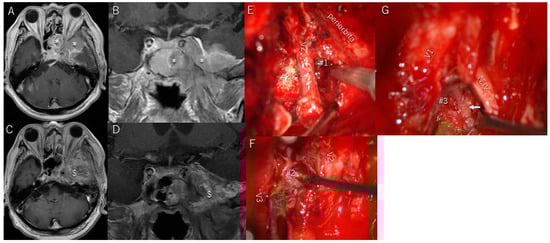

3.6. Illustrative Patient Cases